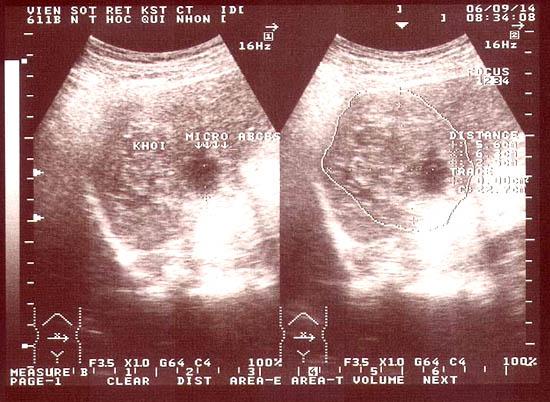

Điều này chứng tỏ các microabces này đã hoại tử, hoặc giai đoạn vừa hoại tử vừa tiến triển có xu hướng lan rộng hoặc quy tụ thành một khối dịch lớn. Đặc biệt, các tổn thương nhu mô gan thường có nhiều “mắt nhỏ”, dạng nốt, nếu là hình ảnh giảm âm hay xen kẻ trống âm ở giữa thì thường không/ hoặc rất khó phân biệt với các dạng áp xe hay khối tân sinh ở gan (hepatic neoplasm) khi đã xuất hiện đặc điểm hoạt tử trung tâm trong nhu mô gan như một số tác giả đã từng mô tả (H.H. Quang và cs., 2005; M. Teke và cs., 2014). Song song với các tổn thương trên, nghiên cứu này có thể nhìn thấy nhiều microabces nằm rải rác trong nhu mô, thậm chí sát bao gan, xen kẻ ổ áp xe là vùng trống âm.

Bên cạnh đó, tổn thương giai đoạn cấp tính còn thấy tổn thương nhu mô nhưng sát bao gan (1,41%), mặc dù kích thước các ổ này rất bé (chừng 1,2 - 1,5cm) nhưng trên lâm sàng bệnh nhân đau rất dữ dội; ngược lại, cho dù kích thước ổ tổn thương có đường kính rất lớn, thậm chí đến gần 10cm, song chúng lại nằm trong lòng nhu mô thì bệnh nhân lại ít đau hơn hoặc thậm chí không đau, và cần chú ý rằng do bênh nhân không đau trong thời gian dài như thế khiến cho ổ tổn thương càng lớn hơn.

Loại tổn thương thứ hai mà chúng tôi hay gặp trong thời gian đầu của cấp tính là các khoảng trống như “khoang” hoặc có nhánh trông giống đường hầm, các dạng tổn thương này nhìn rõ nét hơn nếu so sánh và đối chiếu trên phim chụp CT Scanner hoặc MRI có bơm thuốc cản quang. Đây là những hình ảnh có ngoại vi ngoằn ngoèo, khúc khủy do quá trình sán di chuyển trong nhu mô gan và trong y văn ký sinh trùng cũng từng đề cập (F.Mansour Ghanaei và cs., 2006).

Loại tổn thương thứ ba là một số tổn thương trong nhu mô /hoặc gần sát bao gan nhưng khi hoại tử đã vở ra bên ngoài được bao gan bọc lại (subcapsular mass), một số ổ này có nguy cơ đe dọa vỡ nếu không can thiệp kịp thời (3,53%), thường gọi là giả u mạch (“pseudohematoma”). Trong quá trình theo dõi, đã phát hiện có 2 ca đe dọa vỡ vào khoang phúc mạc nên đã chuyển can thiệp ngoại khoa cấp cứu do khối máu vượt quá khả năng hấp thụ của cơ thể.

Đôi khi, trong quá trình thăm dò siêu âm, phát hiện một số hình ảnh ít điển hình hơn là dạng giả u hạt, hoại tử có tăng âm ngoại vi và một số khối dạng áp xe không điển hình hoặc hốc/ khoang giả như u mạch thể hang (carvenous hemangioma), tuy không nhiều và phần lớn các khối này đều tiến triển tốt và trở về như nhu mô bình thường sau điều trị đặc hiệu, nhưng thời gian tái tạo nhu mô có dài hơn so với các dạng tổn thương khác.